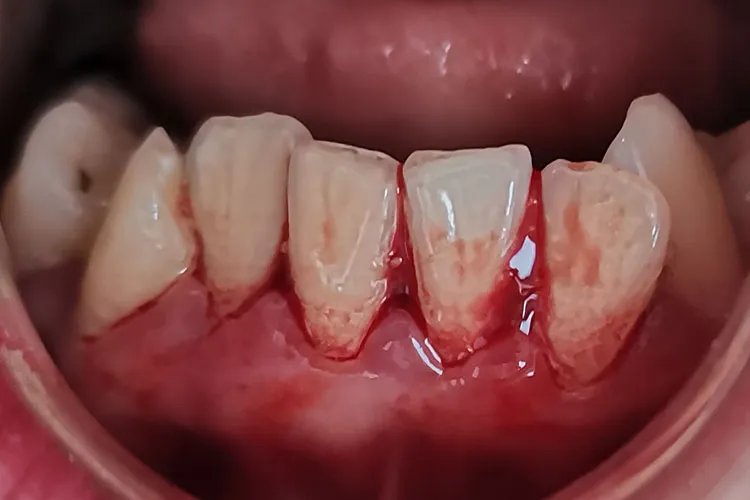

概述牙结石又称牙石,是附着在牙面上钙化的牙菌斑,外观呈白色、棕色或黑色。牙结石的形成主要受唾液成分、饮食习惯、口腔卫生习惯影响。症状牙结石初期较软,因逐渐钙化而变硬,外观呈白色、棕色或黑色,可分为龈上结石和龈下结石。龈下结石牙肉眼不可见,需用探针或X线检查可见。结石过多可刺激牙龈,导致牙龈萎缩,出现牙龈出血、牙齿松动等症状。

病因牙结石是由牙齿表面附着的食物残渣及唾液中的矿物质、坏死脱落的上皮细胞、白细胞等与黏液素以及涎蛋白和脂类混合形成的。口腔卫生习惯不良、常吃细软精细食物、摄入蔗糖过多等都是诱发牙结石的重要因素。诊断主要根据患者的临床表现,以及在口腔内见到牙结石作出诊断。龈下结石可通过探针或X线检查来进行诊断。治疗保持口腔良好的卫生,坚持刷牙漱口,可将刚开始沉积于牙面的牙垢、牙结石及时刷掉。要少吃精细食品,或吃后必须刷牙漱口。还可采用超声波治法去除牙结石,如龈上洁治法、龈下刮治疗法等。